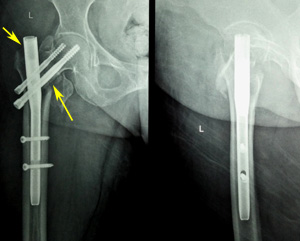

Figure 5b Post-operative radiograph showing varus mal-reduction (pointed by thin arrow as medial overlap of fragments). Also note the superior position of the screws (thick arrow).

Figure 5c Six weeks post-operative radiograph showing varus collapse (thin arrow), cut-out (thick arrow) and fixation failure.

Varus mal-reduction and lag screw cutout

We have 4 cases of varus mal-reduction. Out of these 4 cases, two patients developed cutout, rest of the two went into successful varus mal-union. The 2 cutouts in our study had a fracture classification of 31-A2.3 and 31-A2.2. In addition, the fractures were inadequately reduced and noted to be fixed into a varus position (Figure 5a & b). Placement of hip screw is critical in the ultimate successful outcome of unstable trochanteric fractures. The tip-apex distance (TAD) has been described by Baumgaertner and associates22,23 as a useful intraoperative indicator of deep and central placement of the lag screw in the femoral head, regardless of whether a nail or a plate is chosen to fix the fracture.19 Position of hip screws in head and neck is dependent on quality of reduction. Varus reduction causes placement of hip screws in superior part of head and neck, leading to varus collapse and early cutout (Figure 5b & c). It is important to note that absolute anatomical reduction of unstable trochanteric fractures is a wishful thinking. One should target to achieve antero-medial reduction with correct neck shaft angle. P Janardhana Aithala15 also reported that maintenance of correct neck shaft angle and version leads to union, irrespective of comminution and non-anatomical reduction. Hence, the most important technical aspect of PFN implantation is maintaining the appropriate neck shaft angle so as to place hip screws in desirable position. Both are interlinked as screw placement angle is prefixed and hence unless good neck shaft angle is achieved, it is impossible to put the hip screw correctly. In the AP projection, varus at the fracture site is the main hitch to place the screw in centre or inferiorly, while in lateral projection posterior sagging or flexion of proximal fragment is the problem in putting the hip screw centrally. Several studies have reported a cutout rate of 2%–8%.10,26-31 We observed a cut-out complication in two patients (4.76%). One of them underwent partial hip arthroplasty, whereas the other one opted for implant removal only. Considering the two cut-outs in our study with resultant fixation failure, we believe it is more of technical failure rather than failure of implant. Proper execution of the procedure will give superior results. Our recommendation for lag screw placement position especially in dual screw nails is inferior in AP projection and central in lateral projection.